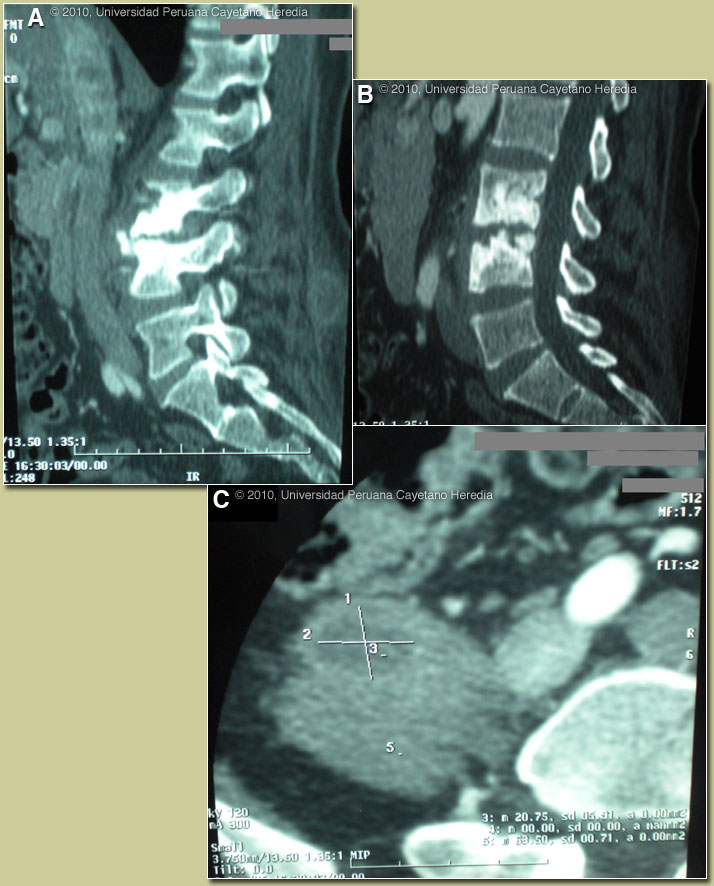

| Diagnosis: Brucella spondylitis with paravertebral abscesses due to Brucella melitensis. |

Serum agglutination test for Brucella was positive at 1/640 with 2-mercaptoethanol positive at 1/320. The diagnosis of Brucella is usually made by serology. In highly endemic areas a slide or tube agglutination test for Brucella is part of the routine initial testing of every febrile patient. The test is cheap, easy to do, and results are available the same day. Blood cultures are expensive and a positive result may take many days, and the sensitivity is only about 70% in Perú (and is lower in most US series), even after 2 sets of blood cultures. Bone marrow cultures are more sensitive (>90%) but are invasive and expensive. In addition, Brucella is a bio-hazard and cultures require biosafety level 3 precautions. The basic agglutination test detects both IgM and IgG antibodies. The addition of 2-mercaptoethanol destroys the binding ability of only the IgM antibody so this test detects the presence only of Brucella specific IgG. With successful treatment, IgG antibody does not often persist at any positive level (≥1/80) for more than a year, and should start diminishing very soon after treatment. Official reading of the CT scan of the spine: disc space narrowing between L3-4, extensive erosive lesions on the anterior-superior angle of L3 (called Pon’s sign) [Image A] and on the articular surface of L3-4 [Image B]. New bone formation with bridging osteophytes is found between L3-4 [Image A]. Marked widening of the right iliopsoas muscle with internal hypodense lesions is demonstrated in Image C. The major differential diagnosis given the fever, night sweats, and these abnormal spine films includes Brucella, TB, and malignancy. Several features of the spine films make the lesions seen diagnostic of brucellar disease: 1) lumbar location; 2) pathognomonic bridging osteophytes between adjacent vertebrae simultaneous with the presence of both osteoblastic lesions and loss of bony mass in the same vertebrae; 3) loss of disk space; and 4) loss of definition of bone at top of the affected vertebrae. Spondylitis may present as the first manifestation of brucellosis (10% in a recent review) and is usually lumbar in location. Iliopsoas abscess is reported in 10% of cases of brucella spondylitis and a paravertebral mass in 46%. On questioning, the patient gave a history of regular ingestion of unpasteurized goat cheese for the last two to three years. This is a frequent scenario in Perú and most countries at highest risk of brucellosis, with the predominant agent being B. melitensis. Brucellosis due to B. abortus acquired from cattle is increasingly uncommon in the US and other countries. All travelers with fevers of unknown origin should be queried for a history of goat cheese ingestion. B. melitensis is commonest in Mexico, Venezuela, Perú, the Mediterranean countries and several of the Arabic countries of the Middle East. The radiologic findings should be contrasted with last week’s case of TB spondylitis [see Gorgas Case 2010-03]. Classic plain x-ray film findings in brucella spondylitis can be found seen in one of our cases from 2001 [see Gorgas Case 2001-02]. Salmonella infection or staphylococcal infections may cause spondylitis and paravertebral abscess but concomitant high fever and systemic illness would be seen. Isolated paravertebral abscesses are most often caused by staphylococci and enteric organisms in the developed world, but tuberculosis and brucellosis, which cause cold abscesses, are reportedly more common causes of paravertebral abscesses in the developing world. Pyomyositis has recently become more common in non-tropical countries in HIV patients and may occur in the psoas muscle. The patient was started on a combination of doxycycline plus gentamicin for 1 week, followed by doxycycline plus rifampin for 11 more weeks. Symptoms subsided after 2 weeks of treatment (fever after 1 week and lumbar pain after 2 weeks). She is able to walk and no residual lumbar pain was observed. Duration of treatment of brucella spondylitis for 12 weeks is recommended in a recent review [Clin Infect Dis. 2008 Feb 1;46(3):426-33], but failures were reported in approximately 15-18%. No differences in outcome were observed whether aminoglycosides were used for the 1-2 weeks or not; however there were only 16 patients in the doxycycline-rifampin group. |